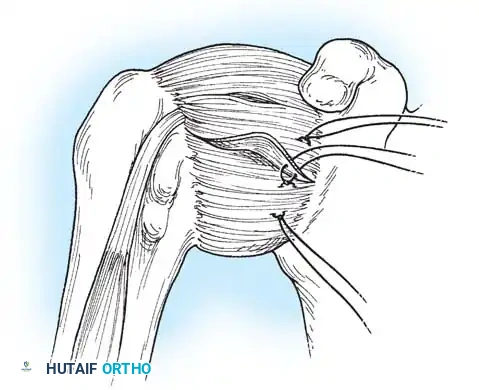

Subscapularis Management

Exposure of the anterior capsule requires navigating the subscapularis muscle. Historically, a vertical tenotomy was performed; however, modern techniques favor a subscapularis split or a peel to preserve the integrity of the muscle belly and its tendinous insertion.

- The Split: A horizontal split is made in the subscapularis at the junction of its middle and inferior thirds, extending from the lesser tuberosity medially.

- Separation: The subscapularis is carefully elevated off the underlying anterior joint capsule. This plane can be scarred in revision cases, requiring meticulous sharp dissection to avoid inadvertent capsulotomy.

Capsulotomy and Joint Inspection

A vertical or T-shaped capsulotomy is performed based on the degree of capsular laxity and the planned shift.

- For a standard Bankart repair with an inferior capsular shift, a vertical incision is made 1 cm medial to the humeral articular margin. A horizontal limb can be added to create superior and inferior capsular flaps.

- Tagging sutures are placed in the capsular flaps for traction.

- A Fukuda retractor is placed within the joint to retract the humeral head laterally and posteriorly, exposing the anterior glenoid rim and labrum.

- Anchor Placement: Suture anchors (typically 3 to 4) are placed along the articular margin of the anteroinferior glenoid (from the 5:30 to 3:00 positions for a right shoulder). Anchors must be inserted at a 45-degree angle to the articular surface to maximize pullout strength and avoid joint penetration.

Capsular Shift and Closure

To address capsular redundancy, an inferior capsular shift is performed.

- The arm is positioned in 30 to 45 degrees of abduction and 20 degrees of external rotation.

- The inferior capsular flap is advanced superiorly and laterally, tensioning the IGHL complex. The sutures from the anchors are passed through the shifted capsule and tied.

- The superior flap is then brought down over the inferior flap in a "pants-over-vest" fashion to reinforce the anterior wall and close the rotator interval.

- The subscapularis split is loosely approximated with absorbable sutures. The deltopectoral interval is closed over a suction drain (if necessary), followed by routine subcutaneous and skin closure.